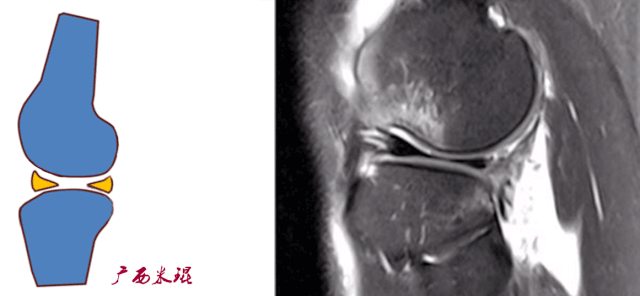

(二)ACL的正常MRI表现

各序列均为低信号。

韧带平直,边界清楚,有较好的张力。

韧带内可有脂肪及滑膜条纹影。

(四)ACL最好的观察层面

最好的观察层面是斜矢状面。

必须结合横断面和冠状面。